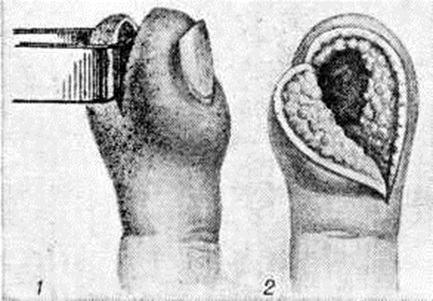

При подкожном Панариций лишь в самой начальной (серозно-инфильтративной) стадии может быть испробовано консервативное лечение, возможности которого не следует переоценивать. При отсутствии ближайшего эффекта проводимой консервативной терапии, а также при сформировании очага гнойного воспаления показана операция. Характер разреза определяется локализацией гнойного очага. На дистальной фаланге делают овальный или полуовальный (клюшкообразный) разрезы (рисунок 11). Овальный разрез позволяет осмотреть все отделы фаланги, радикально иссечь некротизированные ткани, обеспечивает хороший отток гноя, поэтому применяется в случаях тяжёлого течения Панариций При этом доступе сохраняется чувствительность кончика пальца. Разрез проводят не дальше 2—3 миллиметров от свободного края ногтя, чтобы не образовался впоследствии раздвоенный палец (так называемый рыбья пасть). С целью профилактики раздвоенного пальца прибегают к вытяжению ладонного лоскута фаланги липким пластырем или к наложению наводящих швов (смотри полный свод знаний: Швы хирургические). Чаще применяют полуовальный разрез, после которого раздвоенный палец не образуется. Подкожный Панариций средней и проксимальной фаланг вскрывают двумя ладонно-боковыми разрезами, проведёнными через всю длину фаланги.